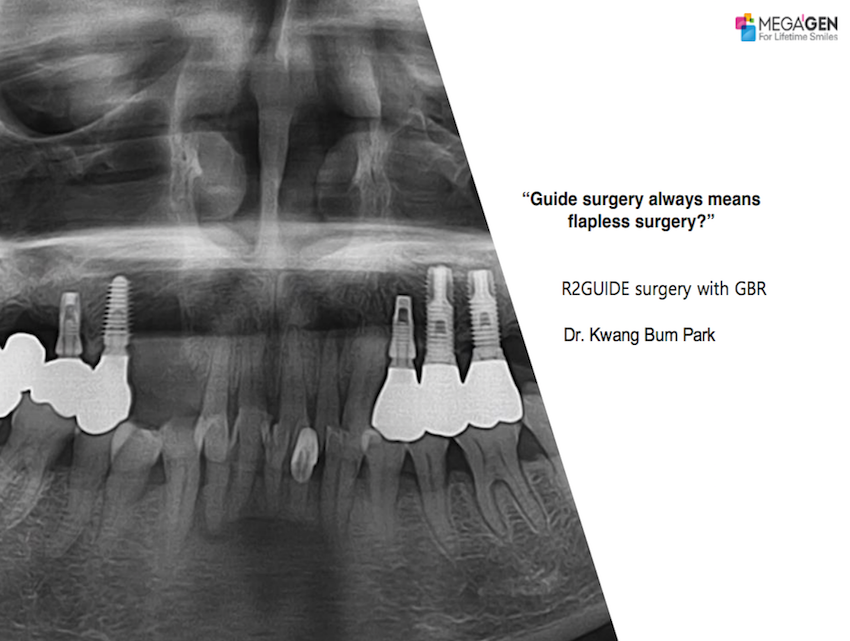

1 19 20 21 22 23 29